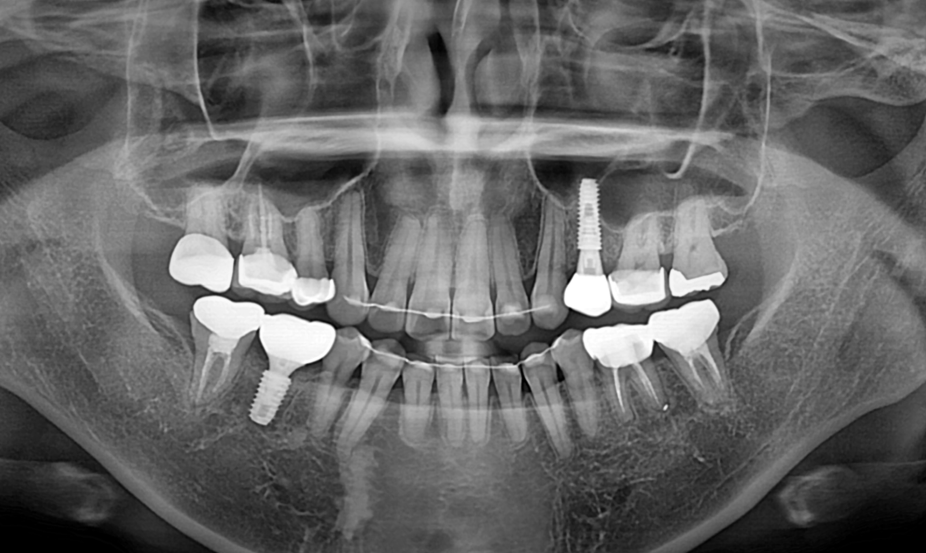

발치 즉시 임플란트.

After